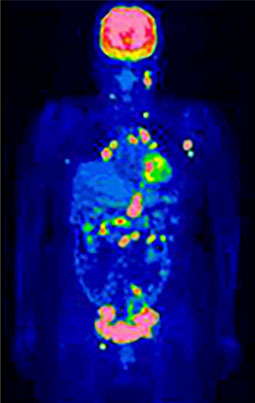

④がんの進行度、転移・再発の有無を確認できます

がんの恐いところは、離れた臓器に転移したり、治療しても再発してくる場合があることです。

しかもがんの転移や再発がどの臓器に出現するかを予測することは大変困難です。

一度の検査で全身をみることができるFDG-PET検査は、がんがどの程度まで拡がっているかといった、がんのステージを判断(病期診断)したり、思わぬ場所への転移や再発がないかどうかを調べるのに役立ちます。

これらを確認することは、その後の治療方法を決めるのにとても重要です。

PET検査による病状の把握で治療方針が変わることも少なくありません。

治療後経過観察にて以前の病変近傍に新たな病変出現(再発)

悪性リンパ腫